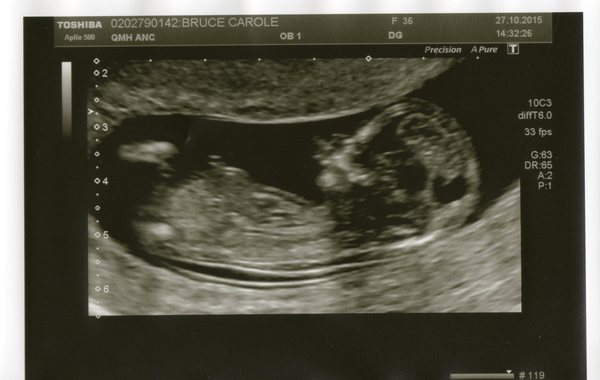

vicky I was found to have a fibroid in my last pregnancy, there didn't seem to be any implications unless it was too near the cervix. Oddly at my scan this time they couldn't see it! Here's my scan pic.. guesses for boy or girl? My hunch is girl. I thought last time I was having a boy and that was spot on. I've booked a private scan in 2 weeks to confirm as I've no patience! Grin

Stormtr00per - assuming you're a Star Wars fan haha, just showed my scan pic to my brother and he said she looks like Figrin D'an?! It's good your fibroid wasn't an issue! I've had a quick google but am going to try and not read too much until I can speak to my midwife because I don't want to worry too much and obsessively look up things that could go wrong like I have done previously!

And here's the best photo we got - have cleaned it up a bit so we can see a bit more, she looks fed up :D

The weird shadow is because she's all hunched up as high as she can get like she's trying to escape up through my stomach! Also because of my weird shaped uterus and how I was lying on my side. Basically everything about it was "weird" today haha

I think boy storm - again no real reason behind it, just going by shape of the head, love seeing everyone's pics :)

vicky yes I have a weird spot encroaching into my ear Shock I feel so unglamorous :( I think your baby looks like a girl, it's a cute photo, I wasn't as impressed with mine as I was with the private scan ones though. Did you get given a date for your 20 weeks scan?

I think boy for Southy and Storm and girl for Vicky! Lovely scan pics!

I'm guessing a boy for Southy and girls for Vicky and Storm [disclaimer: I have no idea about nubs!]